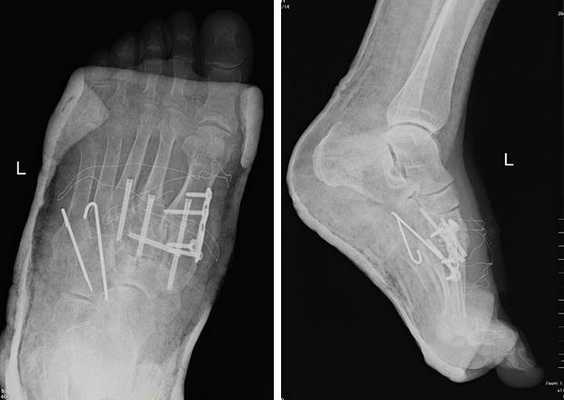

(Справа) Этому же пациенту были выполнены открытая репозиция и внутренний остеосинтез. При рентгенографии среднего отдела стопы в передне-задней проекции видно, что для обеспечения стабильности суставов требуется фиксация множества костей. Следует отметить наличие винта, который выполняет функцию поврежденной связки Лисфранка.

На данной рентгенограмме представлено очень серьезное повреждение стопы, возникшее следствие высокоэнергетической травмы. Результатом травмы стал вывих в суставах среднего отдела стопы).

Рентгенограмма стопы после лечения

Внутренняя фиксация. Данная операция заключается в восстановлении нормального положения (репозиции) костных фрагментов и фиксации их пластинками или винтами. Поскольку пластины и винты будут фиксировать и суставы, в которых норме существует небольшая подвижность, некоторые из этих металлоконструкций в последующем необходимо удалить. Сроки удаления конструкций в зависимости от решения хирурга могут варьировать от 3 до 5 месяцев после первой операции.

Открытое вправление вывиха, трансартикулярная фиксация 1-2-3 предплюсне-плюсневых суставов винтами.